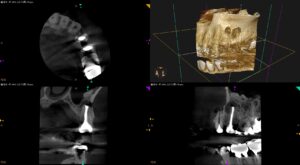

歯茎が腫れたような感じがして熱を持って痛い。噛む時違和感もある〜#12,13 Core build up w/wo Fiber Post→Apicoectomy

紹介患者さんの治療。 主訴は、 歯茎が腫れたような感じがして熱を持って痛い。噛む時違和感もある。 である。 歯内療法学的検査(2025.8.25) #11 Cold+2/2, Perc.(-), Palp.(-), BT … 続きを読む 歯茎が腫れたような感じがして熱を持って痛い。噛む時違和感もある〜#12,13 Core build up w/wo Fiber Post→Apicoectomy